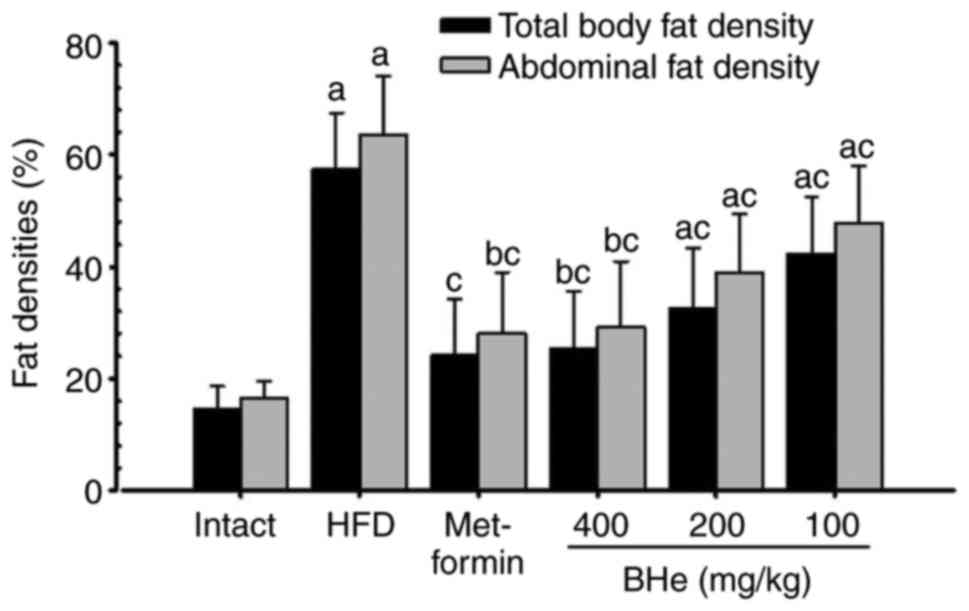

Significant (P<0.05) increases in the total body

fat and abdominal fat density was observed in the HFD control mice

compared with in the intact control, whereas a significant

(P<0.05) decrease in the total body and abdominal fat density

was observed in all treatment groups following analysis via live

DEXA. Specifically, all doses of BHe resulted in clear

dose-dependent decreases in the total body and abdominal fat

density compared with in the HFD control mice (Figs. 3 and 4). The mean total body fat density was

increased by 295.14% in the HFD control group, with changes of

−58.03, −26.29, −43.12 and −56.10% in the metformin (250 mg/kg) and

BHe (400, 200 and 100 mg/kg)-treated groups, respectively. A-55.96%

decrease in the mean abdominal fat density was observed in the HFD

control group, with changes of −55.96, −24.78, −38.78 and −54.12%

in the metformin (250 mg/kg) and BHe (400, 200 and 100

mg/kg)-treated groups, respectively.